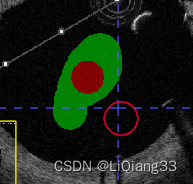

Active Label为激活的标签,表示当前使用的标柱类型,此时选择label 1为红色,说明使用红色进行标注paint Over为允许标注的范围,All labels允许对所有的标签进行标注,包括覆盖之前的标注;All visiable label是对所有可见的标签进行标注,如图,红色所在的位置则不能标注,

paint over续:使用Active Label=Label1; paint Over=Clear Label标注时,只允许对没有标注的区域标注,如图,同样的,如果paint over=Label1(red), active label = label3则蓝色只能在红色上标注